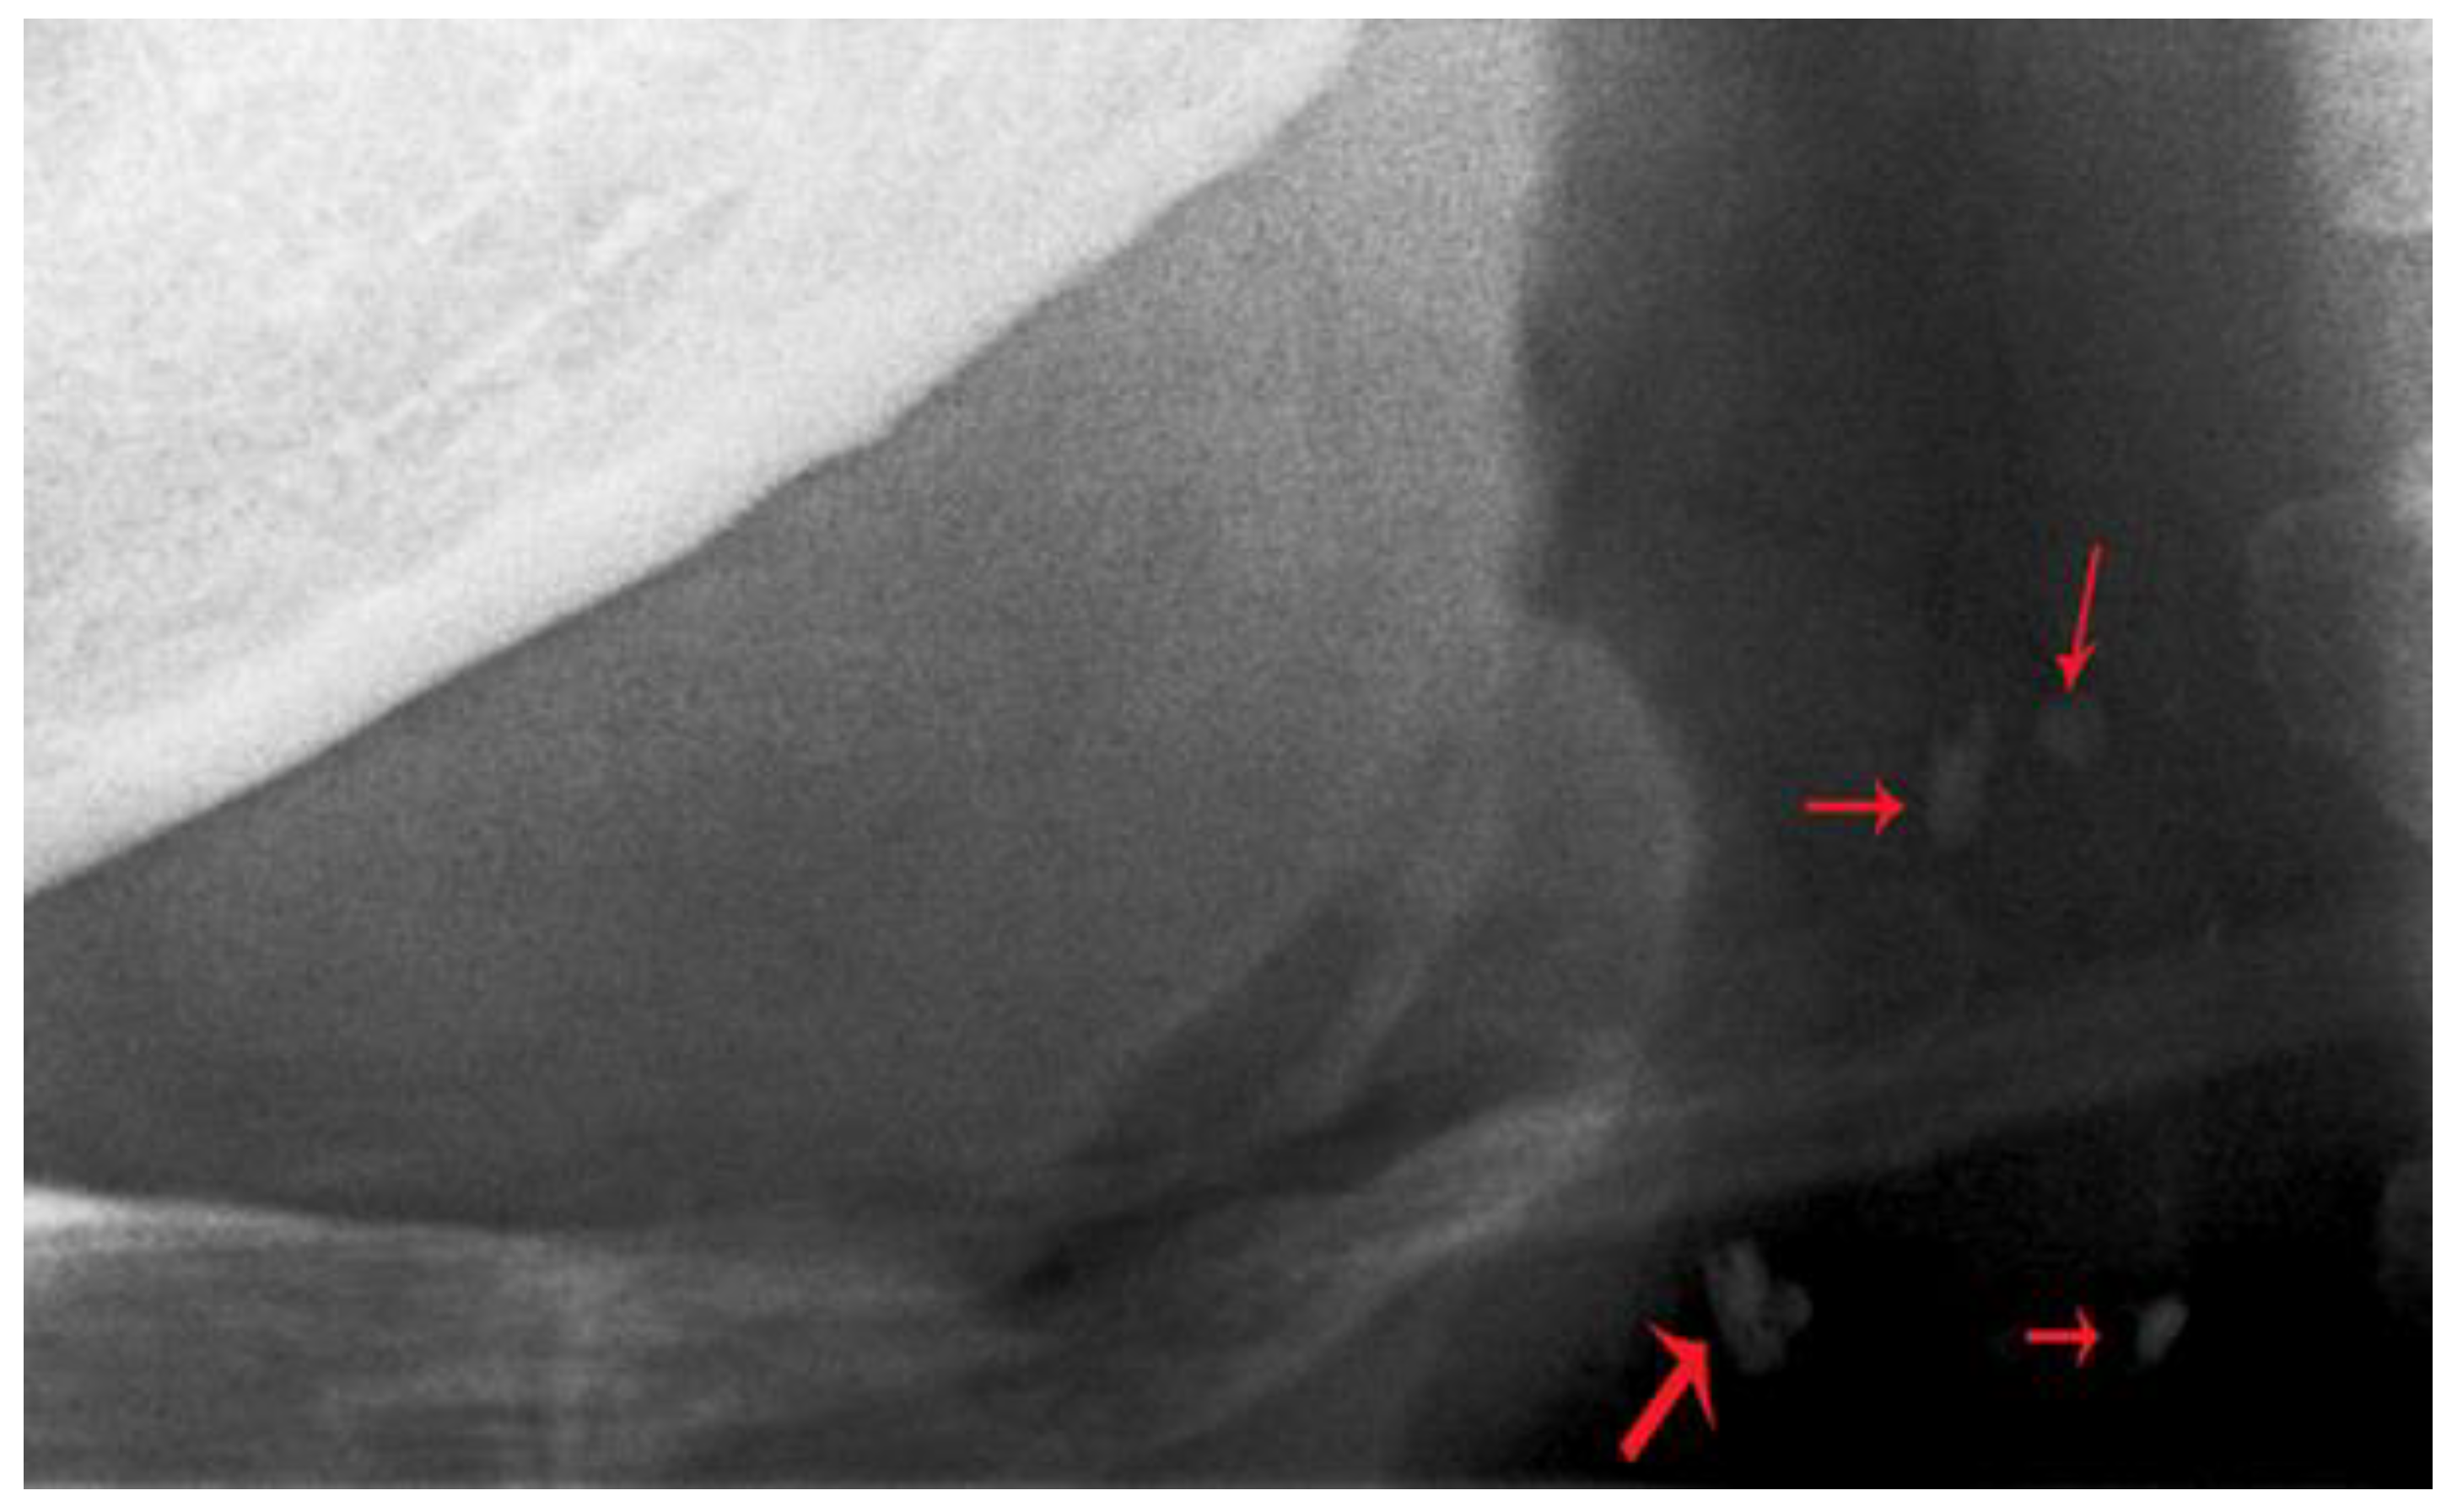

2.2. Radiograph Evaluation